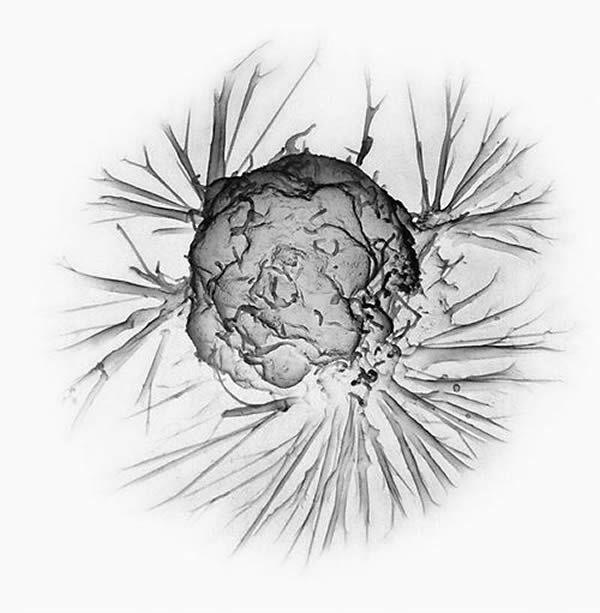

乳腺癌细胞电镜照